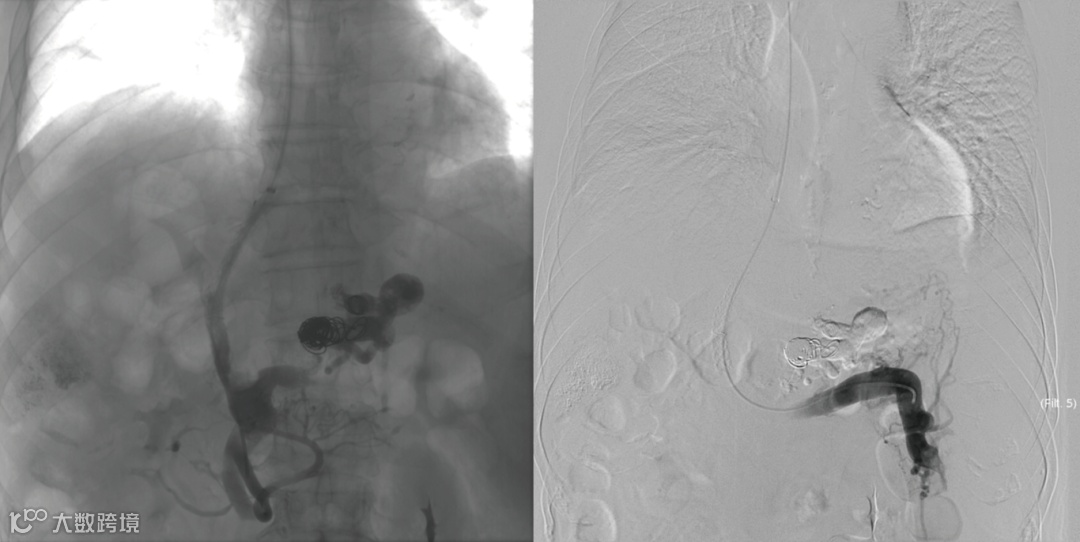

建立门体静脉分流道后行门静脉、脾静脉造影

胃冠状静脉造影

超选择插入至曲张静脉,注入弹簧圈栓塞至血流明显减缓

超选择插入至曲张静脉,注入弹簧圈栓塞,后经微导管注入聚桂醇至曲张静脉血流基本停滞

术后造影(即刻效果):胃底曲张静脉血管网未见显影